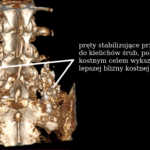

Instrumentacja tylna

- Wprowadzenie śrub pedikularnych jedno- lub obustronnie,

- Wstępna stabilizacja.

Ostateczna stabilizacja

- Montaż prętów,

- Kompresja segmentu,

- Kontrola osi i wysokości przestrzeni międzykręgowej.